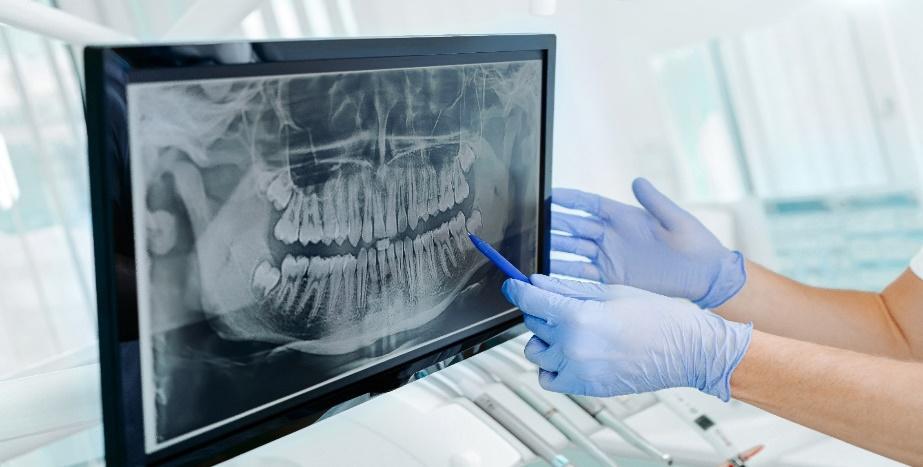

Panoramic dental x-ray

Panoramic X-Rays

Unlike other kinds of dental x-ray, which capture just one tooth or a section of the mouth, panoramic x-rays show the whole mouth in one single image. Dental radiography helps us identify dental issues that would otherwise be difficult or impossible to spot. These include:

• Tooth decay, especially under a tooth filling or between two teeth

• Tooth infections, including abscesses at the end of a tooth root or below the gum line

• Impacted wisdom teeth

• Bone loss in the jaw bone from gum disease or a missing tooth

• Hyperdontia and hypodontia (the conditions of having too many or too few teeth genetically)

• Tumors linked to jaw cancer or oral cancer